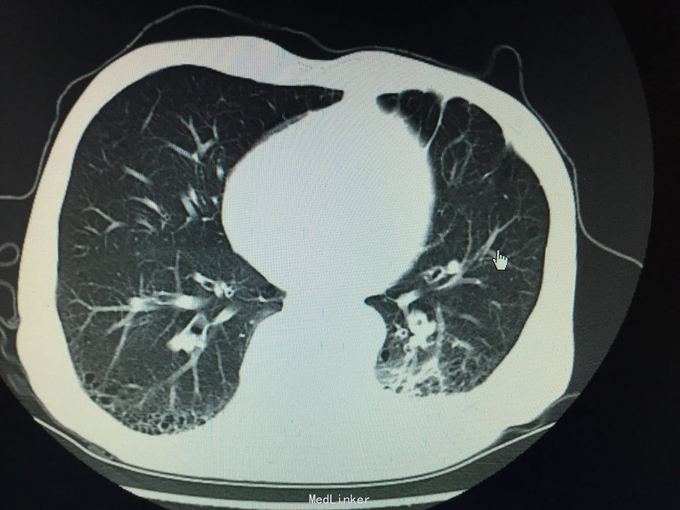

MRI示:肋骨,胸椎多发骨转移 CT示:胃Ca术后:腹膜后淋巴结转移,左侧胸膜多发转移,左侧后壁转移并T10锥体及左侧横突,第10.11后肋转移骨质破坏,骨质疏松并T12及L2压缩骨折 核医学ECT示:多发骨转移